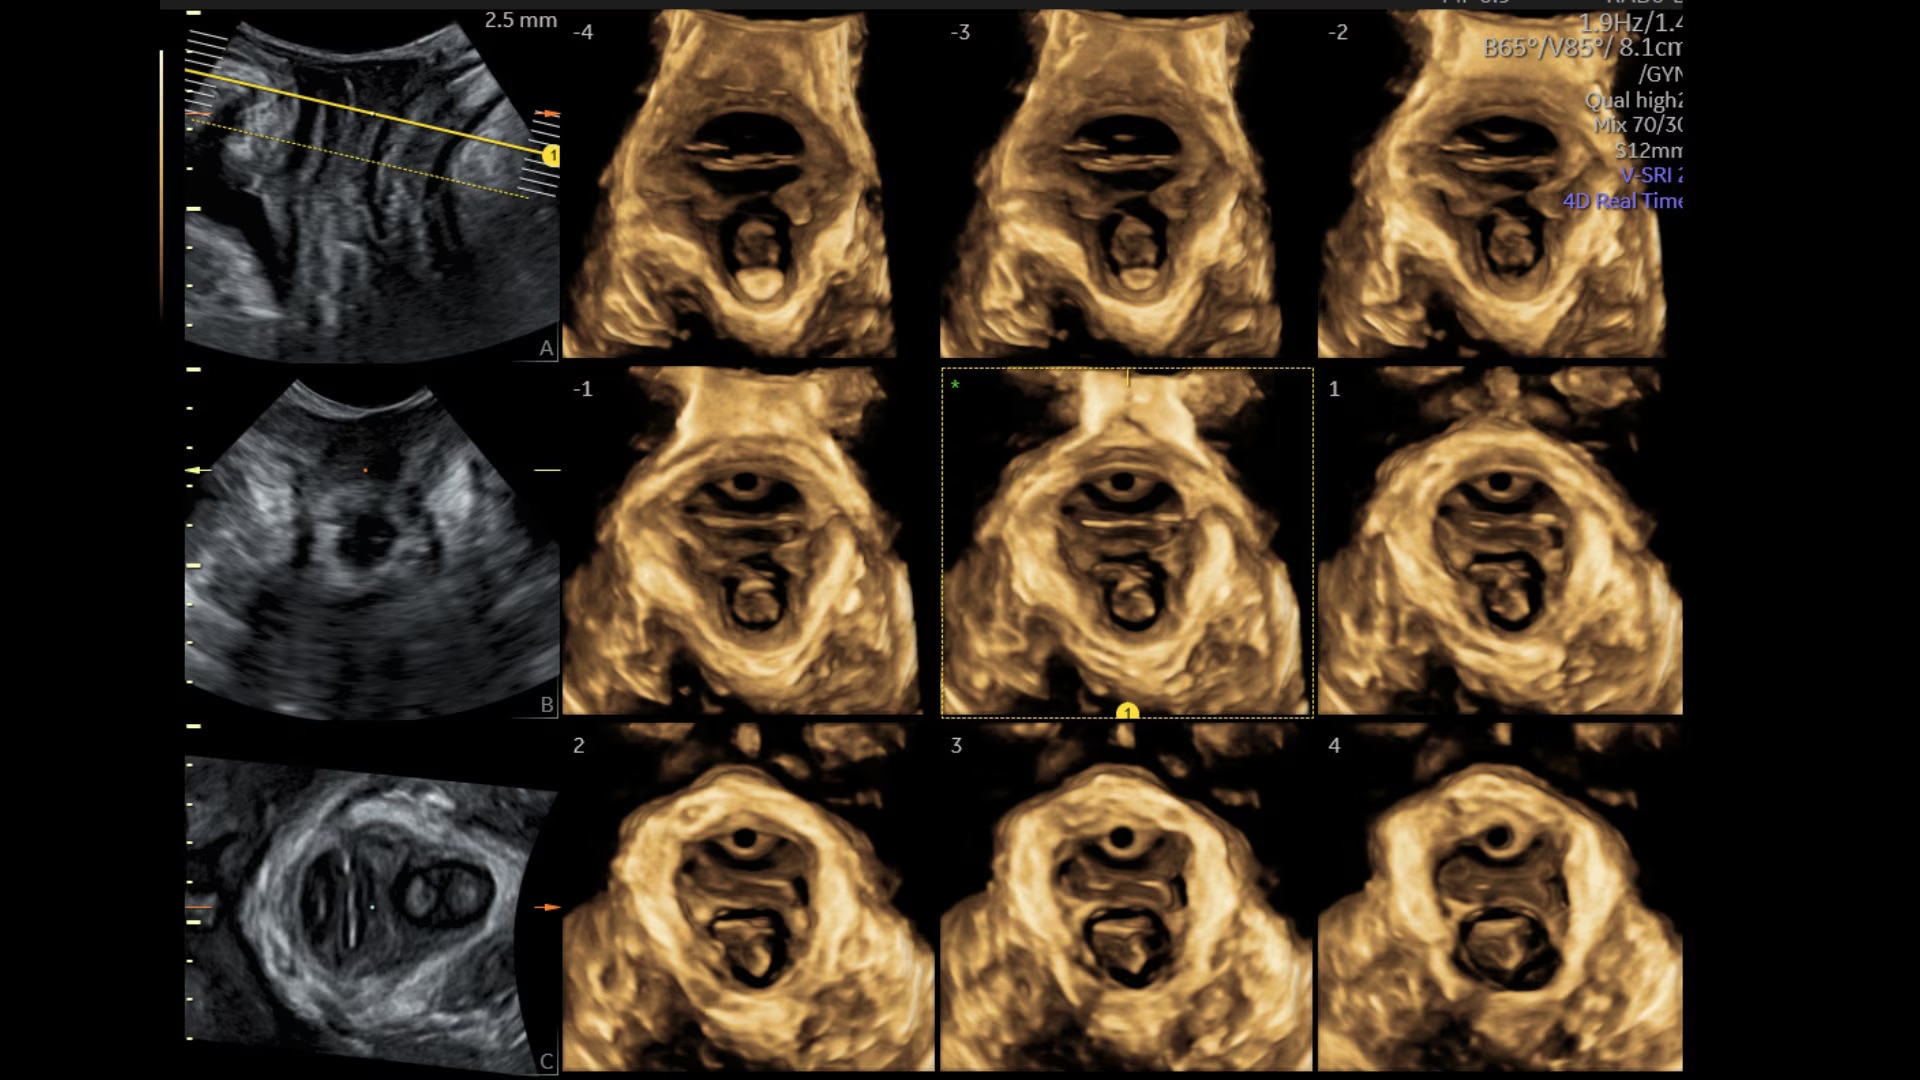

Sonopelvicfloor

Assess pelvic floor anatomy using guided workflow & AI

Using a guided workflow and AI, SonoPelvicFloor:

• removed exam complexity by automating plane alignment and measurements

• can reduce keystrokes by up to 75% and offer users a time savings of up to 80%